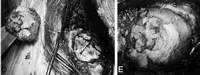

沙特阿拉伯King Faisal大学的神经外科医师介绍了一种简单而安全的颅骨重建方法。该方法用病人自体的骨屑,组织胶和凝胶泡沫片,混合塑形后重建颅骨切除术后患者的外科缺损(如图示)。

该重建术要求尽可能多的收集颅骨切除术中产生的骨屑,加入组织胶,将其放置于两层凝胶泡沫片之间,塑造成与外科缺损吻合的形状后,将塑造好的骨屑团置入颅骨缺损处。